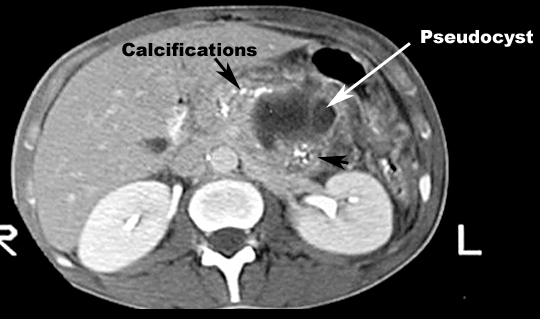

Pancreatitis with Pseudocyst and calcifications

Mass density in pancreas

• White arrow: Psudocyst

• Black arrow: Calcifications